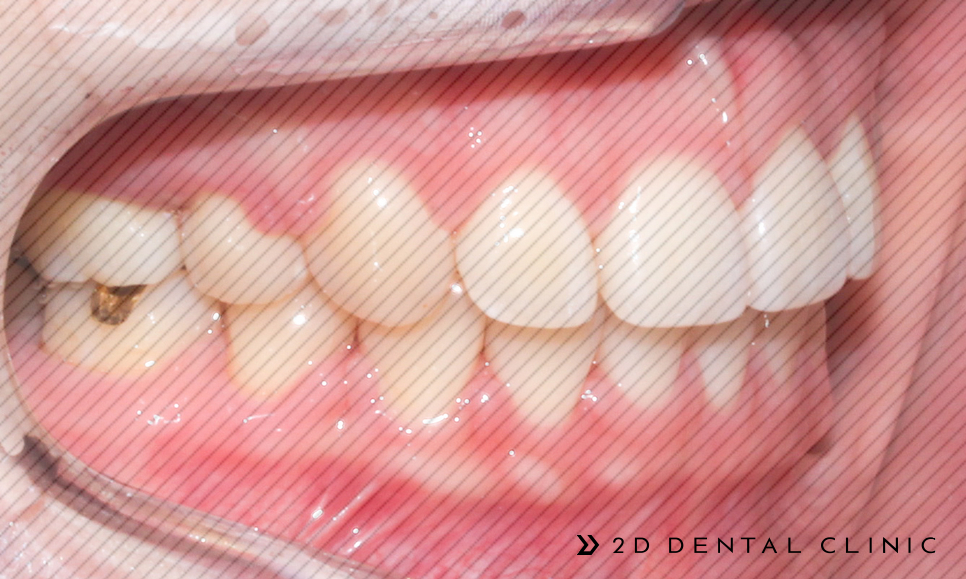

이번 케이스로 찾아주신 환자분은 돌출입 개선 및 덧니 케이스를 개선하고자 투디치과를 찾아주신 분이랍니다.

환자분의 경우 상악의 크라우딩이 심하여 발치교정이 필요하신 분이셨는데요~!

전체 교정인 클리피씨로 진행되었고 상악의 양쪽의 제1소구치를 발치하였습니다. 제2 대구치는 미니스크류로 당겨드렸고요.

전체적인 크라우딩의 개선

교정기간은 1년 반이 소요되셨답니다~ 전체적인 크라우딩이 개선되고 치아 배열이 고르게 개선되었습니다.

코와 턱 이어지는 E라인을 잡아드려 퉁명스러울 수 있는 인상이 개선됨이 보입니다.